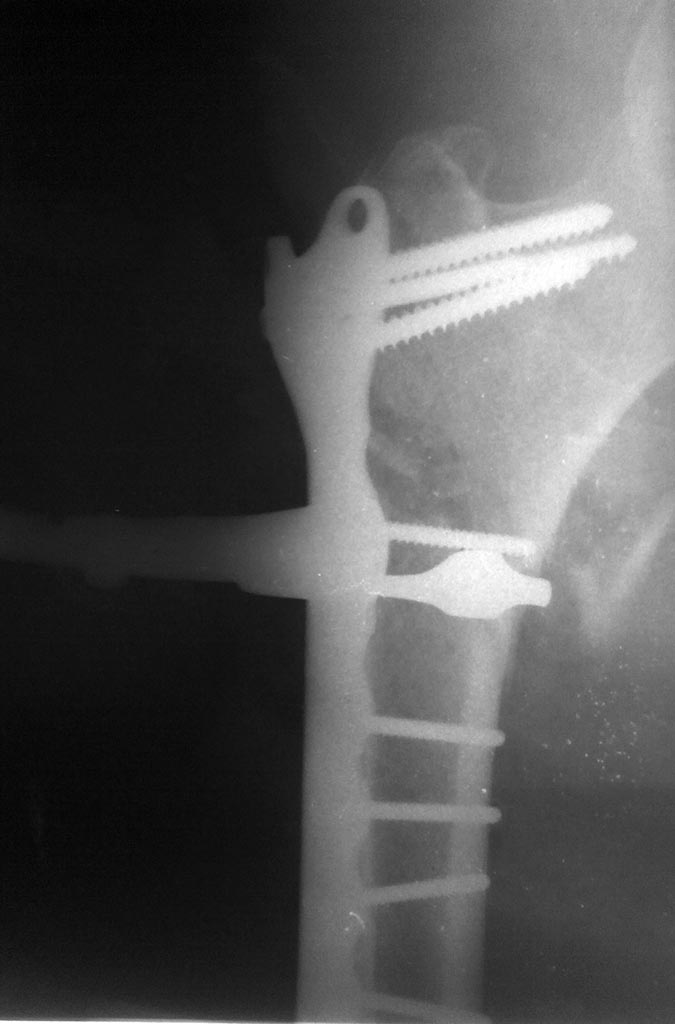

Хотелось бы посмотреть на свежий снимок оперированного отдела бедра. Может, там все развалилось уже, и это и есть причина лихорадки?

после

В сожалению остеосинтез у Вас получился нестабильным, это, опосредованно, может стать причиной лихорадки. Полностью согласен с постом про УЗИ и ревизию. Хочу добавить, что в случае отсутствия гнойного процесса, можно провести в проксимальный отломок более длинные винты.